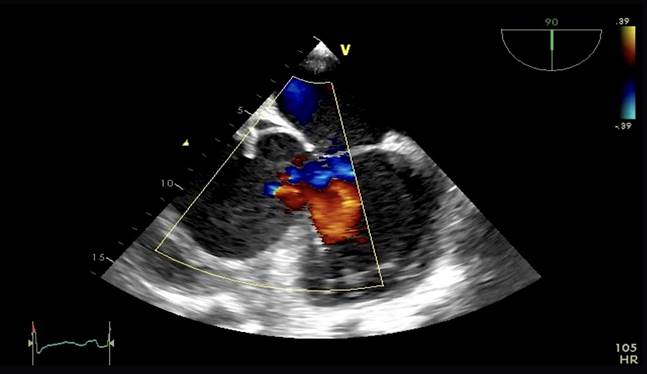

Aproximadamente 3 Semanas posterior al alta presenta cuadro de insuficiencia respiratoria asociado a insuficiencia cardiaca descompensada por lo que acude a nuestro Hospital de Especialidades Abel Gilbert Pontón siendo internada en Unidad Coronaria, a su ingreso se evidencia dolor precordial y torácico bilateral que irradia a región dorsal acompañado de disnea clase funcional NYHA IV/IV, tos persistente y edema leve de miembros inferiores, los laboratorios realizados evidencian anemia leve con hb 10.8 g/dL, péptido natriurético elevado de 12895 pg/ml, enzimas cardiacas negativas, hematuria y proteinuria en uroanálisis; en la radiografía de tórax se muestra cardiomegalia y derrame pleural bilateral; En electrocardiograma taquicardia sinusal, dextrorrotación, complejo QS en cara inferior, sin alteraciones de la onda T y segmento ST. En eco de pleura muestra derrame pleural derecho de moderada a gran cuantía y derrame pleural izquierdo moderado, sospechando de colagenopatía vs enfermedad autoinmune a descartar. Se realiza ecocardiograma transtorácico se evidencia formación aneurismática del VI de 9.5cm x 9.7cm tapizado por trombos con pérdida de la continuidad a nivel perimembranoso septal, además de una miocardiopatía dilatada con FEVI (fracción de eyección del ventrículo izquierdo) 28%. El estudio de líquido pericárdico da como resultado exudado con relación líquido/sérica de LDH 1,8 y proteína 0,7. En ecocardiograma transesofágico (Ilustración 1,2,3) se confirma pseudoaneurisma de gran tamaño del VI en región basal posterior con flujo bidireccional de 10 cm x 7,22cm tapizado de formación trombótica con pérdida de la continuidad de la región basal y posterior del VI con hipocinesia global e hipertensión pulmonar leve con insuficiencia mitral y tricuspidea leve por lo que se decide resolución quirúrgica.

Ilustración 2 Ecocardiograma Transesofágico. Pseudoaneurisma del VI en su porción septal

Fuente: Hospital de Especialidades Guayaquil “Doctor Abel Gilbert Pontón”.

Autor: Dra. María Sánchez Sánchez.

Se realizaron varios rastreos ecocardiográficos para determinar su estructura e incluso verificar su diagnóstico, para nuestro análisis es de gran relevancia el antecedente de la realización de la biopsia con ventana pericárdica. El pseudoaneurisma se encontraba muy posterior y basal comprometiendo al tabique interventricular sitio poco frecuente lo que causó grandes dudas de su afiliación fisiopatológica y del compromiso de ambos ventrículos. El eco transesofágico fue definitorio en este caso siendo una herramienta útil para el diagnóstico de pseudoaneurisma y análisis de secuelas quirúrgicas.